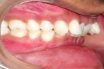

Class II, Division 2 malocclusion

The maxillary central incisors are in linguoversion.